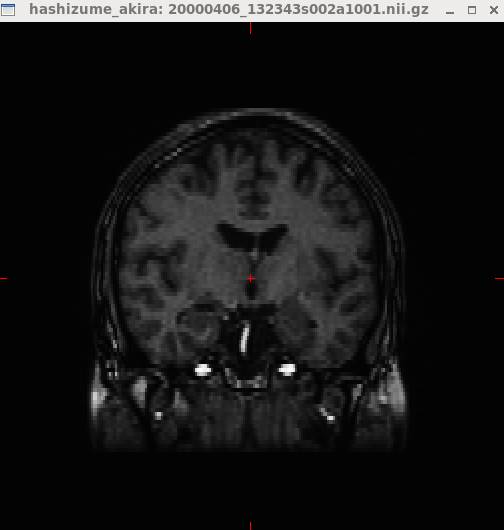

Anatomistで開いたところです。

Windows→Open a 4 views blockをクリックします。

3断面で表示させてみました。